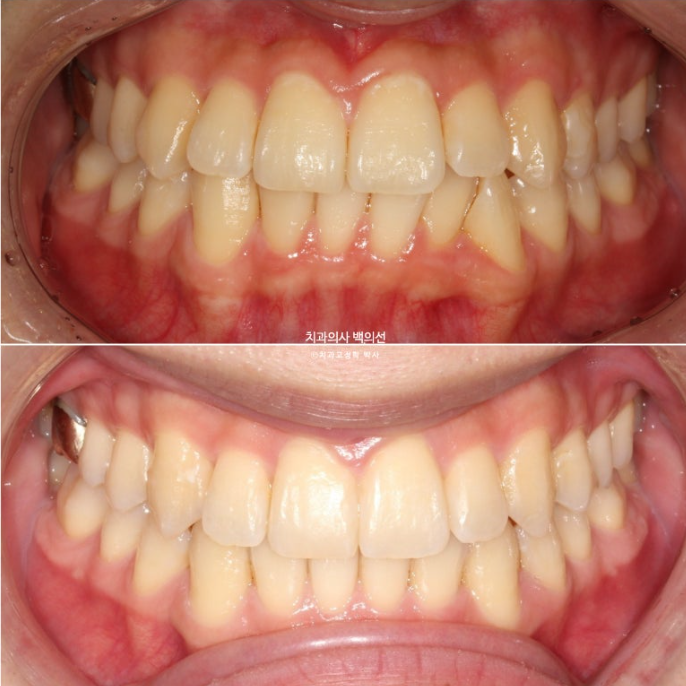

22.10~25.03

뻗쳐있던 앞니와 송곳니가 개선이 되고 스마일라인이 정돈되었습니다.

앞니 기울기와 중심선이 개선이 되니 비대칭처럼 보이던 것도 해소가 되었습니다.